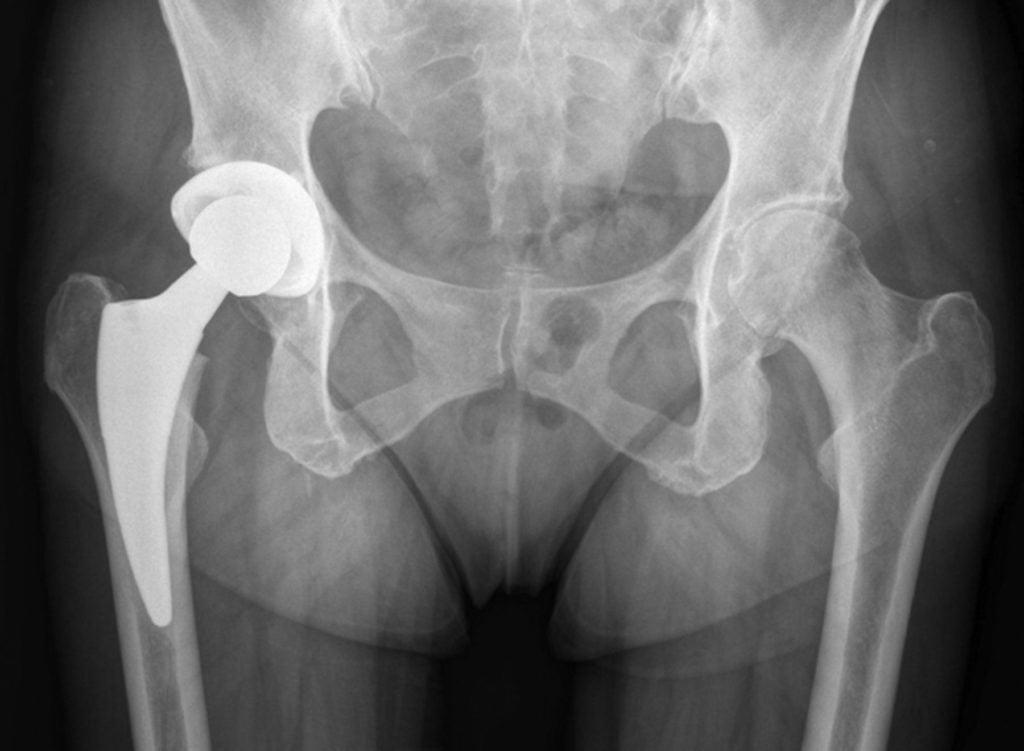

Некоторые люди считают, что МРТ нельзя делать при наличии металлических иплантатов, штифтов и накостных пластин. Однако это заблуждение. Большинство современных металлоконструкций изготавливают из сплавов, которые не разогреваются и не смещаются в магнитном поле.